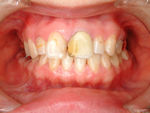

◆メタルボンドクラウン修復

→